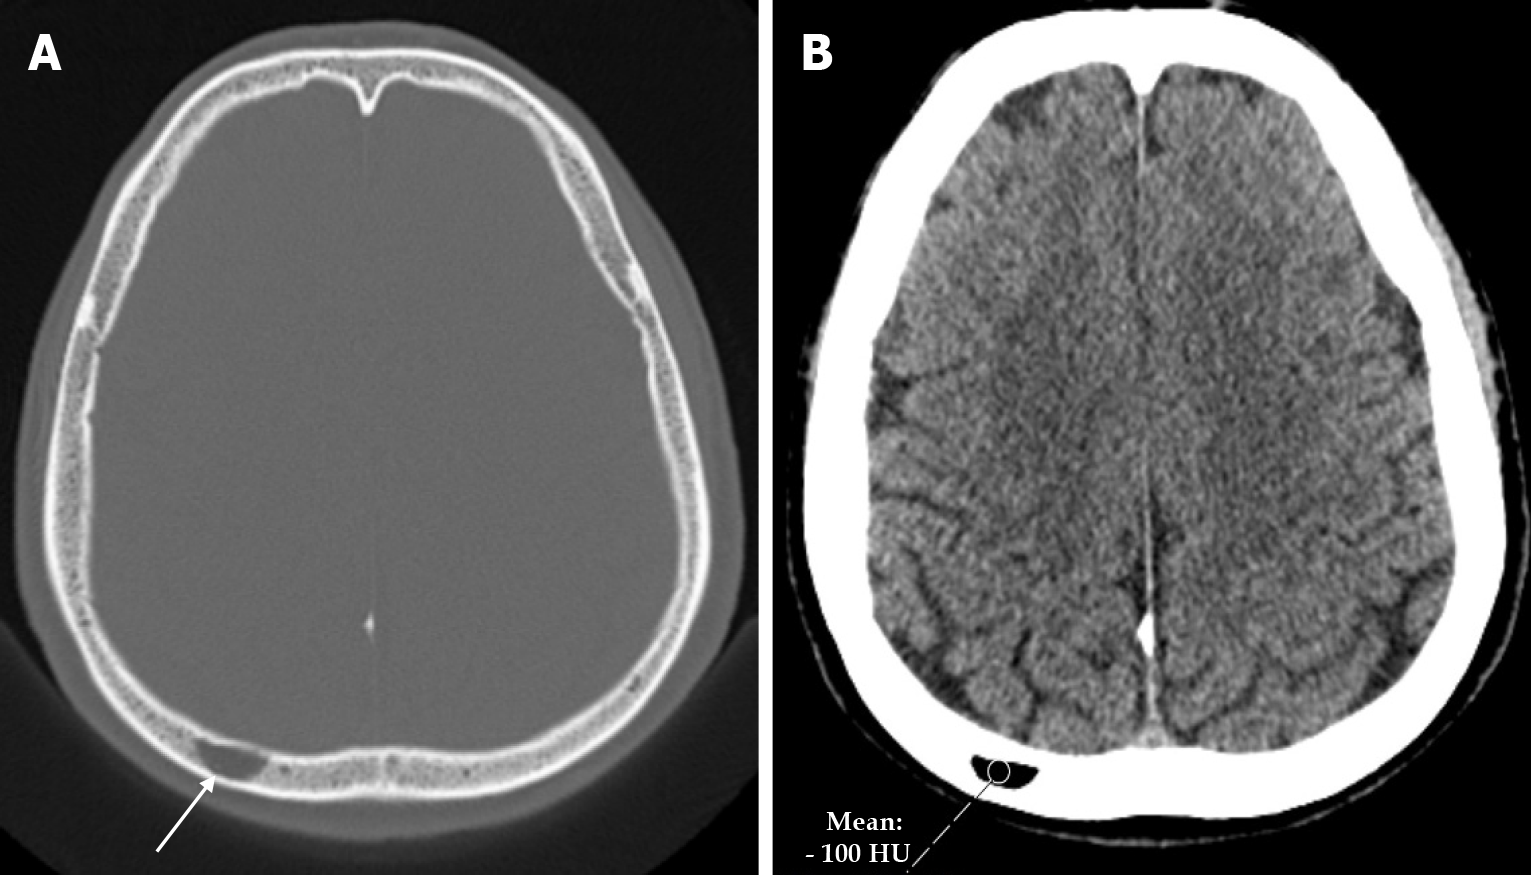

Intraosseous lipoma is a rare benign tumor that accounts for 0.1%-2.5% of all primary bone tumors. Only 4% of intraosseous lipomas are found in the skull. Intraosseous lipomas of the skull are divided into three groups according to their location: Calvarium, skull base, and facial skeleton. It is seen as a radiolucent mass in the skull on plain radiography. On CT it is seen as a spindle-shaped low density mass in continuity with the surrounding diploe (Figure 23), while on MRI it is seen as a homogeneous high signal intensity on T1-weighted and T2-weighted images. Common radiological features include calcification (57%), marginal sclerosis (74%) and cyst formation (67%). Intraosseous lipoma can show various histological changes such as atrophic bone trabeculae, fat necrosis, myxoid stroma and calcification. The differential diagnosis is often intraosseous venous malformation[69].